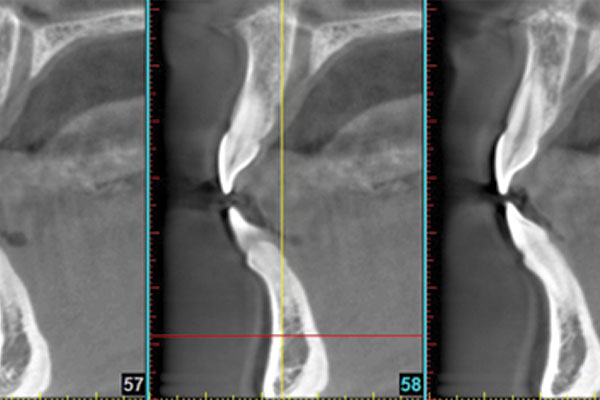

L’immagine più dettagliata permette di effettuare diagnosi rapide e precise, raggiungendo risultati di

maggior successo. Attraverso la Tecnologia 3D si possono studiare le articolazioni temporo-mandibolari in modalità tridimensionale, mentre in ortodonzia le informazioni e i dettagli anatomici ottenuti sono maggiori rispetto a un normale telecranio.